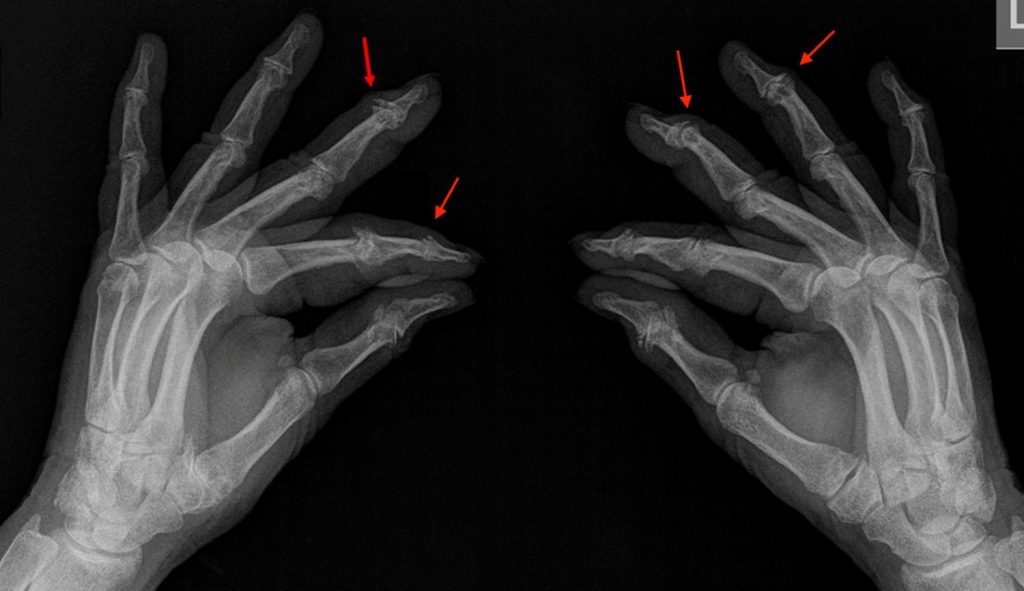

Se basa en la exploración física y la radiografía (Figura 1), donde se evidencian estrechamiento del espacio articular, esclerosis ósea subcondral y osteofitos.